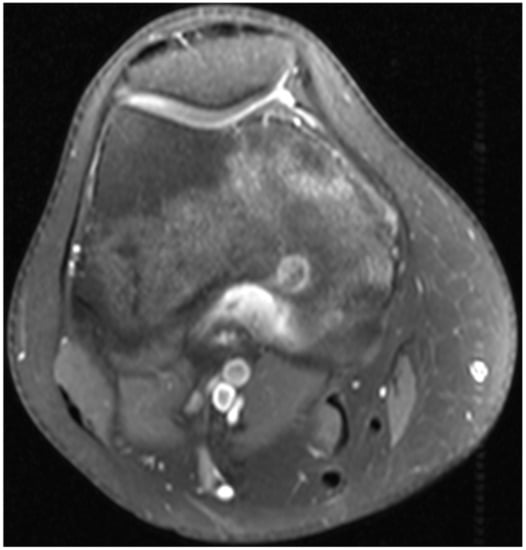

2. Case 1